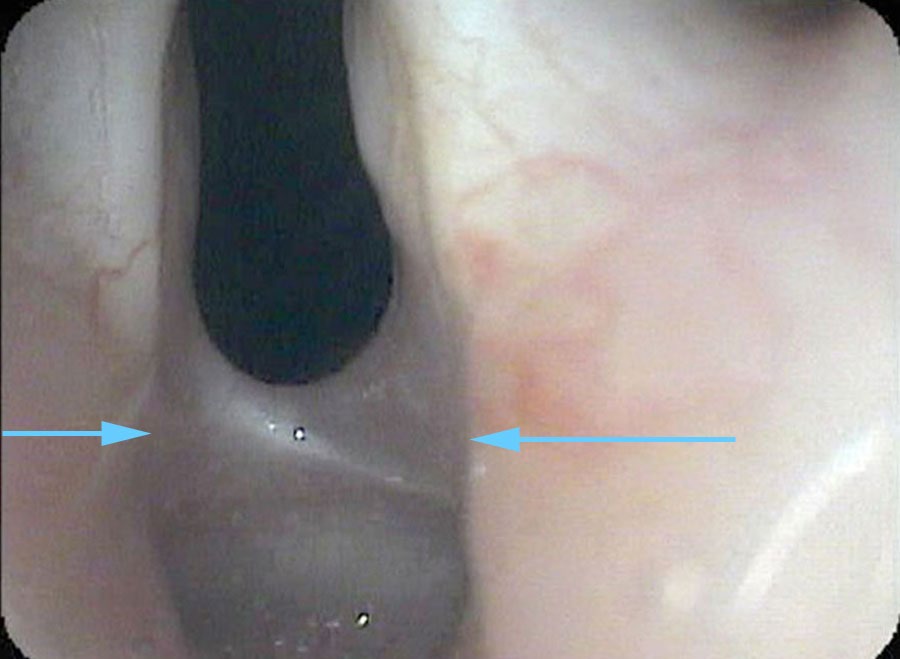

I drip some numbing medication onto her vocal cords and pass the endoscope under the arytenoids at the back of the larynx — looking at the area where the endotracheal tube would have been sitting for 10 days. I find a band of scar tissue just beneath the vocal cords, holding the vocal cords together. At most, she can open her vocal cords about 2 millimeters because of this scar band.

- A scar band (posterior glottic stenosis) from prolonged intubation is mechanically distinct from vocal cord paralysis — but both produce similar-appearing immobility on a standard endoscopic overview.

- Passing the endoscope beneath the arytenoids and very close to the posterior commissure is the only way to directly visualize a scar band in this location.